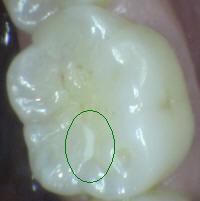

3. CARIES CON EXPOSICIÓN DENTINA

1. CAVIDAD DETECTABLE EXPONIENDO DENTINA

1. ACTIVIDAD

1. activa/inactiva

2. HALLAZGO CLÍNIICO:

1. cavidad en esmalte, con exposición de dentina

2. DIAGNÓSTICO

1. lesión cariosa cavitacional con exposición de dentina

2. TRATAMIENTO

1. operatoria

1. promoción y prevención

2. CRITERIO DE DIAGNOSTICO

1. cavidad detectable con dentina visible esmalte opaco o decolorado exponiendo dentina

1. ICDAS 5